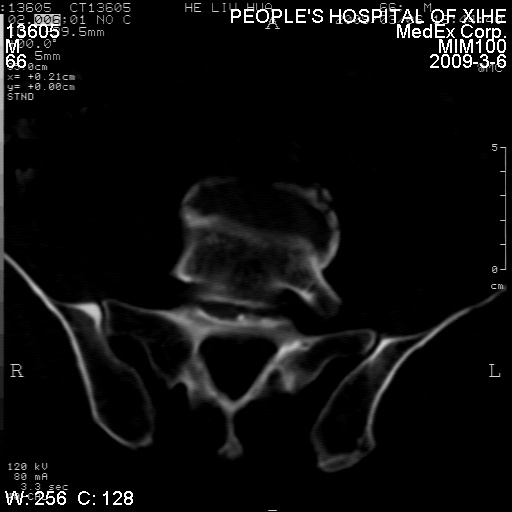

标题: CT18522:男,66岁。考虑结核有错吗 [打印本页]

标题: CT18522:男,66岁。考虑结核有错吗

x线片示:骶骨密度增高。

考虑----腰椎骶化-----退变-----椎管狭窄

退行性变,椎体滑脱

腰椎滑脱并有退变

退行性变,椎体滑脱。建议同椎体平行进一步扫描。